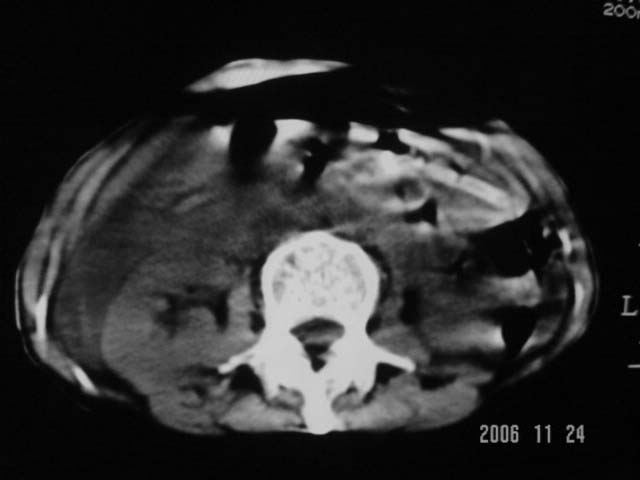

仰卧位见:肝前间隙及肝脾间隙内可见新月形气体密度影,边缘清楚,侧卧位见气体随体位改变而移动,ct值约-929hu。膈下、肝下间隙及部分肠间隙可见液性密度影。考虑:1、上腹部空腔脏器穿孔,以胃穿孔可能性大。2、少量腹水。

仰卧位见:肝前间隙及肝脾间隙内可见新月形气体密度影,边缘清楚,侧卧位见气体随体位改变而移动,ct值约-929hu。膈下、肝下间隙及部分肠间隙可见液性密度影。考虑:1、上腹部空腔脏器穿孔,结合临床,首先考虑胃穿孔可能性大。2、少量腹水

补充--肝门及肝肾间隙以见积气显示。

支持消化道空腔脏器穿孔(腹腔内大量游离气体影,小网膜囊内亦见气体影),少量腹水。